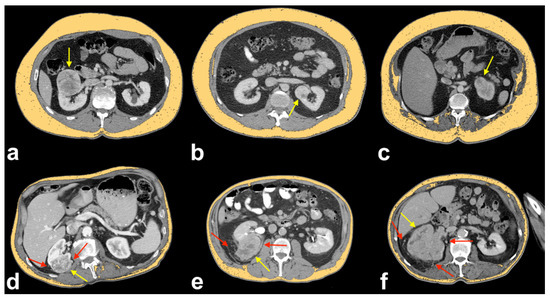

The presence of collateral vessels in renal cell carcinoma (RCC) is considered a sign of locally advanced disease (i.e., pT stage > T3a) [12]. However, this finding can be present in the early stages of RCC (Figure 1).

Figure 1.

Axial CT image with maximum intensity projection (MIP) reconstruction showing ccRCC with T1a of locoregional staging (yellow arrow) and peritumoral collateral vessels (red arrows). Note that peritumoral collateral vessels can be present also in patients with early disease stages.